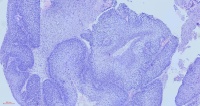

鼻咽肿物

性别年龄59岁临床诊断鼻咽肿物真菌性鼻窦炎

一般病史CT:双侧咽隐窝及咽鼓管开口无变窄,咽鼓管隆突未见增厚,双侧咽旁间隙清晰。左上颌窦内见结节状软组密度影,大小约3.7cm×3.7cm,增强扫扫描呈欠均匀强化,邻近左上颌窦壁见骨质吸收、破坏,部分骨质增厚且密度增高呈骨质硬化改变;左上颌窦内软组织密度影,考虑低度恶性肿瘤与真菌性鼻窦炎鉴别,建议活检;

标本名称鼻腔病损

大体所见灰黄碎组织,质中

免疫组化结果: MDM2(-),CDK4(-),Ki67约60%(+),CD34(-),S100(-),SATB2(+),SMA(-),Desmin(-),P40(上皮+),EGFR(上皮+),CK(上皮+),EMA(上皮+),Vimentin(+)。

癌,没问题。

考虑:鼻咽癌(鳞癌)

鳞癌,非角化型。